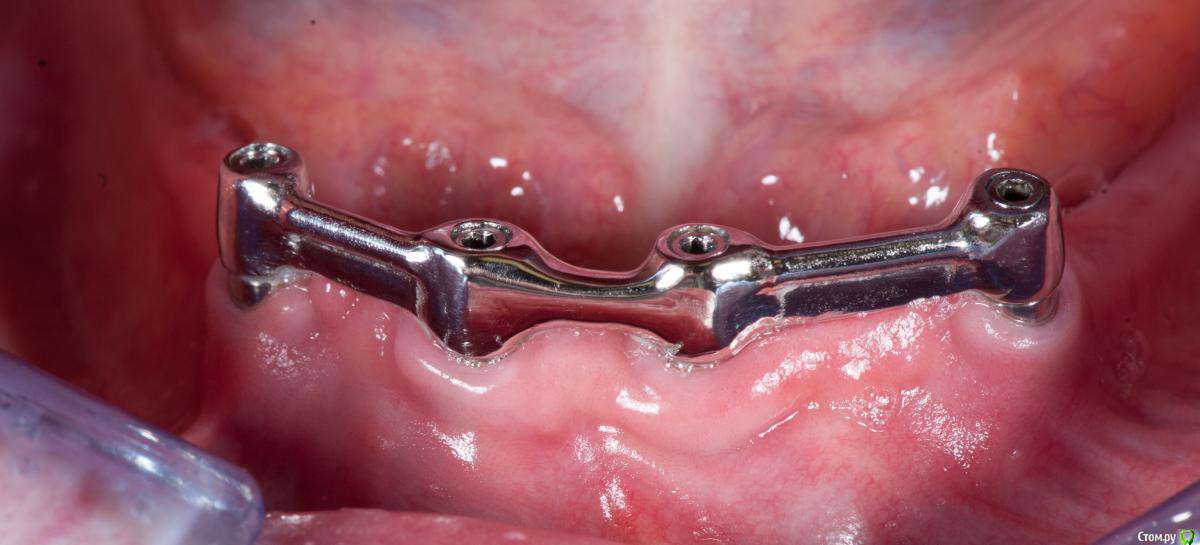

Doc Опубликовано 5 февраля, 2017 Поделиться Опубликовано 5 февраля, 2017 13 лет назад. Ссылка на комментарий

Doc Опубликовано 5 февраля, 2017 Поделиться Опубликовано 5 февраля, 2017 А это вот сегодня. Гигиена, кажется, хромает, но стоят почему-то. Ссылка на комментарий

Doc Опубликовано 6 февраля, 2017 Поделиться Опубликовано 6 февраля, 2017 2 балки в смыле слева на 2 импланта и справа такую же? Почему бы не одну как показали ниже? В моей практике так делали 1 раз при большом расстоянии между медиальными имплантами наверху Док, замки к балкам не добавляете? Ортопеды с кем работал/работаю делают в основном с замками бредент, один работает только с мк-1, и сейчас с сикуралоками начали работать. Есть у балок без замков преимущества перед балками с замками? По комфорту, долгосрочному прогнозу...Очень интересно ваше мнение. На приведенных фотографиях как раз две балки с матрицами, а посередине просто связано для прочности, в середине нет никаких матриц. Замки не добавляем, ибо не вижу в этом никакой необходимости. Приведенные выше варианты работают более чем достаточно и для прочной фиксации (иногда даже ослаблять приходится, не все могут снять) и для долговечности. Сделал таких протезов не один десяток, до сих пор менял матрицы два-три раза, остальные так и ходят со старыми, все прекрасно держится.Перестал делать такие конструкции только из-за появления "все на четырех". Теперь нет смысла мучаться со съемными, если с тем же количеством можно получить несъемный вариант. 2 Ссылка на комментарий